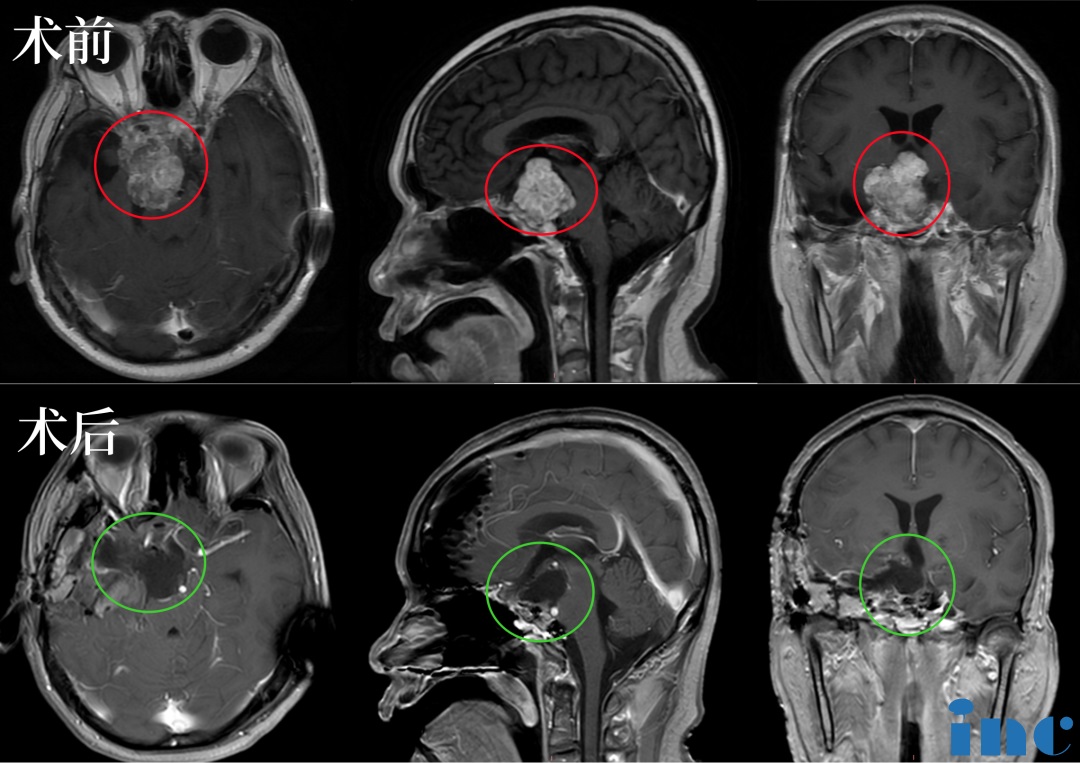

48岁男性较大脊索瘤复发,“双镜联合”成功手术

26岁男士较大颅颈交界区脊索瘤压迫脑干,福教授双镜联合全切巨型脊索瘤

21岁女性颅颈交界区脊索瘤